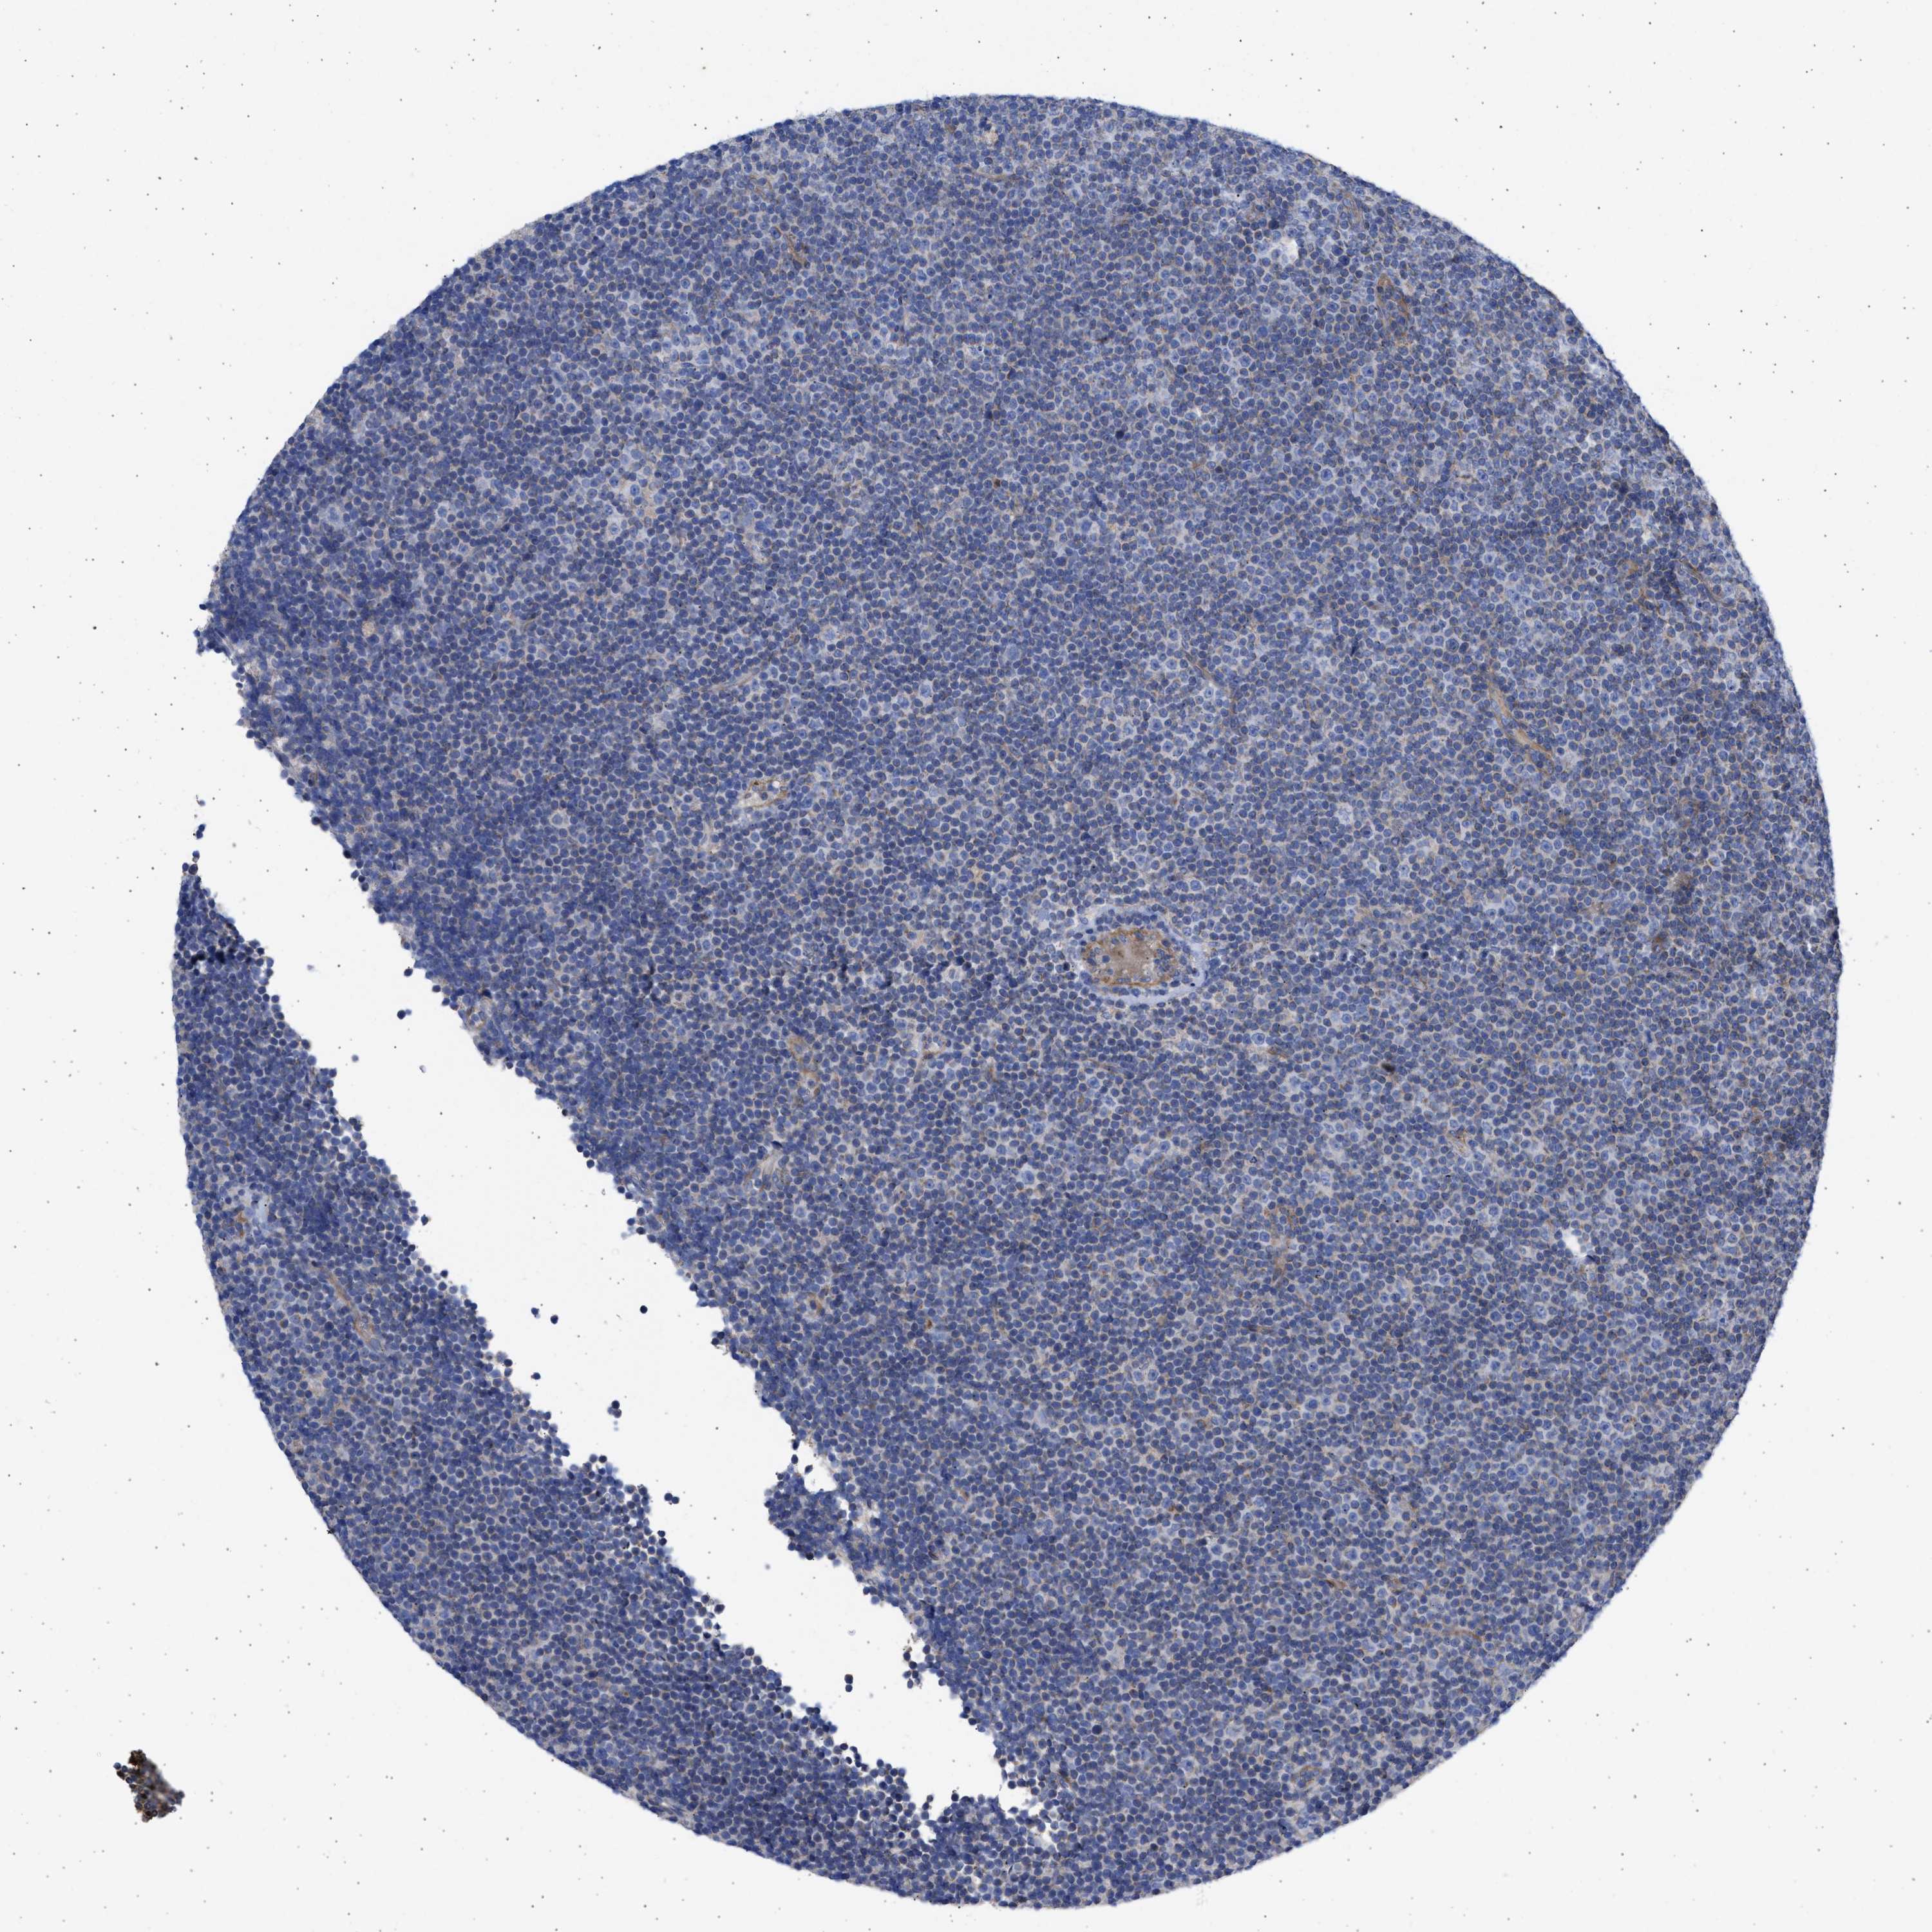

CANCER LYMPHOMA Show tissue menu

LYMPHOMA - Protein expressioni

A mouse-over function shows sample information and annotation data. Click on an image to view it in a full screen mode. Samples can be filtered based on level of antibody staining by selecting one or several of the following categories: high, medium, low and not detected. The assay and annotation is described here.

Each image is clickable and will lead to virtual microscopy that enables deeper exploration of all samples and also displays staining intensity scores, fraction scores and subcellular localization as well as patient and tissue information for each sample.

Antibody HPA018400

Staining

High

Medium

Low

Not detected

Intensity

Strong

Moderate

Weak

Negative

Quantity

>75%

75%-25%

<25%

None

Location

Nuclear

Cytoplasmic/membranous

Cytoplasmic/membranous,nuclear

Hodgkin's disease, NOS

Malignant lymphoma, non-Hodgkin's type, High grade

Malignant lymphoma, non-Hodgkin's type, Low grade